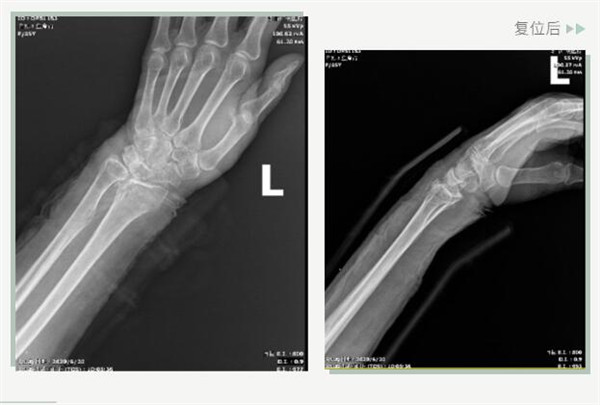

復(fù)位前

25日當(dāng)天,莊阿婆來(lái)到危立軍副院長(zhǎng)門診,經(jīng)拍片顯示,莊阿婆左橈骨遠(yuǎn)端粉碎性骨折,左髂骨至髖臼后緣及恥骨下支骨折??紤]到莊阿婆年紀(jì)較大,基礎(chǔ)病較多,難以經(jīng)受手術(shù)創(chuàng)傷,傳統(tǒng)手法復(fù)位更為合適。推、拽、按、捺……經(jīng)過(guò)危立軍副院長(zhǎng)一番手法復(fù)位后,再次拍片顯示莊阿婆橈骨遠(yuǎn)端骨折端復(fù)位位置良好,莊阿婆及其家人感到非常滿意。

復(fù)位后